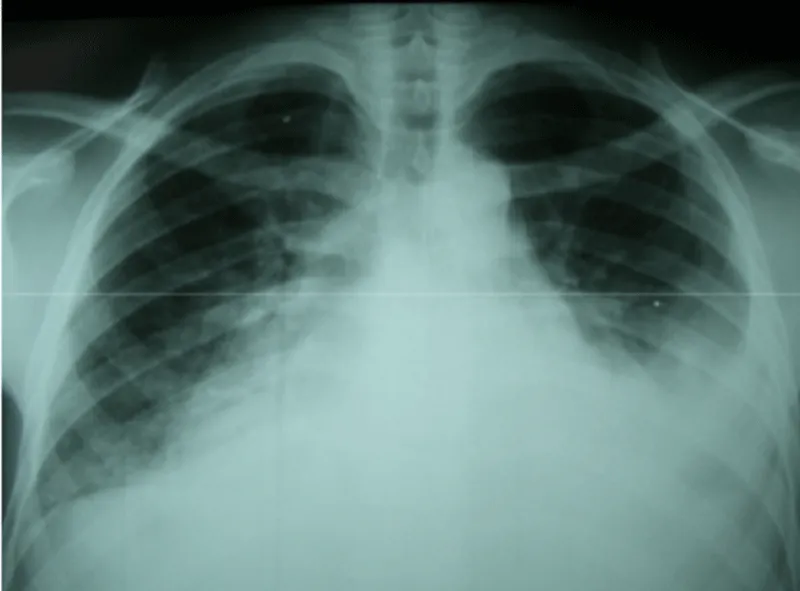

After sternotomy and opening of the pericardium which was thickened, an effusion with false membranes is revealed. There was no obvious bleeding point, and the point of break-in could not be objectified. After initiation of routine cardiopulmonary bypass, aortic cross-clamping and adequate myocardial protection, the mitral valve was exposed through a trans-septal approach, we revealed a 2 cm perforation in the anterior mitral valve (Figure 2). After suturing the defect (Figure 3), we proceeded to posterior mitral ring reduction by suture annuloplasty.

Figure 2: Perforation of the body of the anterrior mitral valve (white arrow).